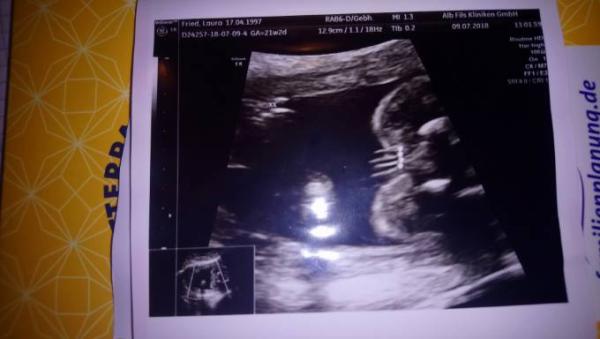

Hallo Ihr Lieben, ich war gestern in der 18. Woche zu einem Ultraschall und die Ärztin hat eine Tendenz geäußert, was es werden könnte. Jetzt wollte ich Euch mal fragen, ob Ihr was klares erkennen könnt? Ich verstehe von den Ultraschallbildern nämlich leider nicht allzu viel. Ich weiß nur, dass das Bild von unten gemacht wurde und man den Popes sieht :) Danke schon mal. LG diddi

Bild zu Erkennt Ihr an dem Bild das Geschlecht? - Schwanger - wer noch? Rund um die Schwangerschaft

Würde nun auf Mädchen tippen. Wenn es von unten Popo Gemach würd, finde ich sieht das wie Schamlippen aus.

Ich tippe auf Mädchen. Sehe da drei Striche, was für Schamlippen spricht. Aber sicher ist es eh erst, wenn das Baby auf der Welt ist.

Hä? Ich sehe da eindeutig einen großen Hodensack, zwei Hoden und den Schniedel wo soll da ein Mädchen sein

Hier nachgezeichnet, nicht professionell, aber das was ich sehe

Also ich habe mir mal ein paar andere Bilder von Jungen oder Mädchenoutings angeschaut und von meinem Eindruck her hängt aber immer bei Jungs naja der Schniedel irgendwie rum und das fehlt finde ich irgendwie bei meinem Ultraschallbild, auch wenn es schon irgendwie nach Hodensack aussieht da wo die Pobacken sind. Aber auch das habe ich bei Mädchenoutings gesehen, dass die auch etwas rundes hatten, wo die Pobacken sind. Also es bleibt weiterhin leider ein Rätsel. LG

Hallo Ihr Lieben, ich hätte da auch eine Frage zu meinem Ultraschall ich erkenne nichts darauf... Was meint Ihr? Dad bild wurde in der 21 ssw aufgenommen:D

Bild zu